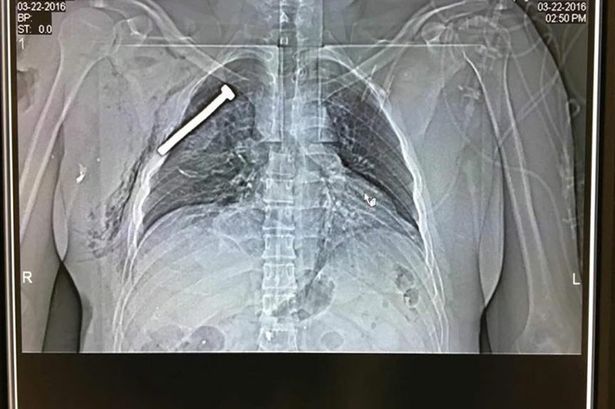

Σοκ προκαλούν οι φωτογραφίες που δόθηκαν στη δημοσιότητα από τα μεταλλικά αντικείμενα που βρέθηκαν στα σώματα των τραυματιών από τις τρομοκρατικές επιθέσεις των Βρυξελλών.

Οι γιατροί αφαίρεσαν από τα τραύματα βίδες, καρφιά και άλλα μεταλλικά αντικείμενα.

Τα ευρήματα αυτά επιβεβαιώνουν τις πληροφορίες που από την πρώτη στιγμή είδαν το φως της δημοσιότητας ότι οι τρομοκράτες πυροδότησαν βόμβες γεμάτες καρφιά και βίδες προκειμένου να μεγιστοποιήσουν τον αριθμό των θυμάτων τους.